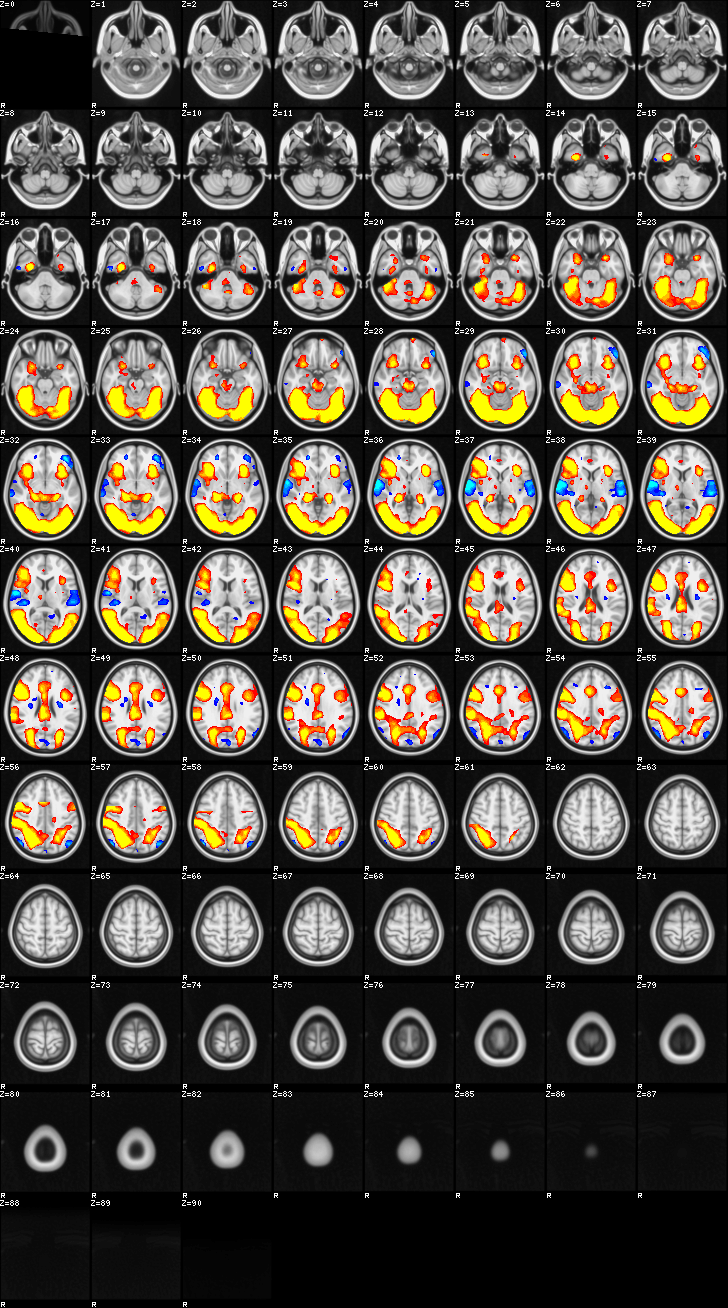

Mixed Effect (flame1)¶

ATM it is 26 subjects, 8 mm FWHM spatial (simple gaussian) smoothing, preliminary results only

Images thresholded abs value > 2.3 and colormap goes from 2.3 to 5 (red->yellow) or -2.3 to -5 (blue->lightblue)

03-self¶